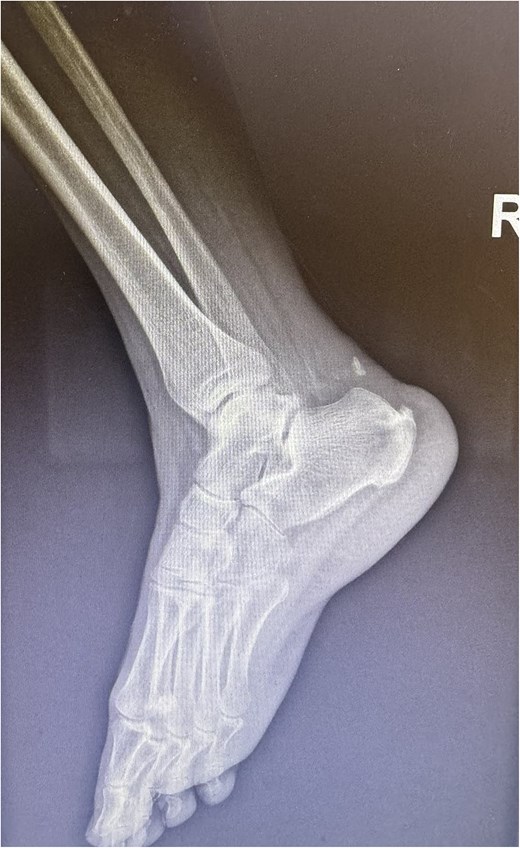

A comprehensive physical examination provided significant insights into the patient’s condition following the Achilles tendon rupture. The Thompson test was particularly noteworthy, showing an absence of plantar flexion upon calf compression, strongly indicating a complete tendon rupture. The examination further revealed a palpable gap in the Achilles tendon and increased passive dorsiflexion. Symptoms included significant weakness, difficulty walking and heel pain. Imaging studies, including X-rays (Fig. 2) and magnetic resonance imaging (MRI) (Fig. 3), confirmed these findings, showing an acute rupture with retracted tendon edges, distinguishing it from chronic condition and suggesting a possible link to the vigorous ultrasound therapy [3].